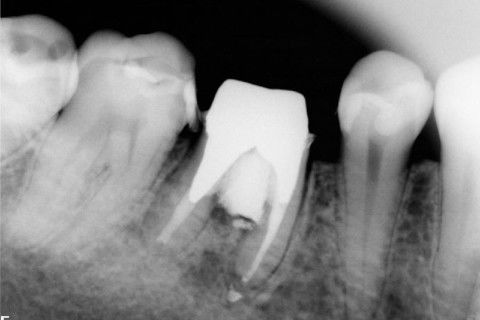

Retratamento de Canal, Tratamento de Perfuração, Restauração Provisória com Resina, Núcleo e Provisório.

RETRATAMENTO DE CANAL, TRATAMENTO DE PERFURAÇÃO, RESTAURAÇÃO PROVISÓRIA COM RESINA, NUCLEO E PROVISÓRIO.